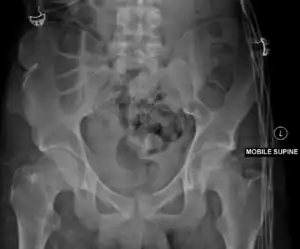

Malgaigne's fractureJoseph-François Malgaignevertical pelvic fracture through both pubic rami and the ilium or sacroiliac joint with vertical displacementhigh energy impact to pelvis (front to back)Malgaigne's fracture Archived 2017-11-02 at the Wayback Machine at TheFreeDictionary.com